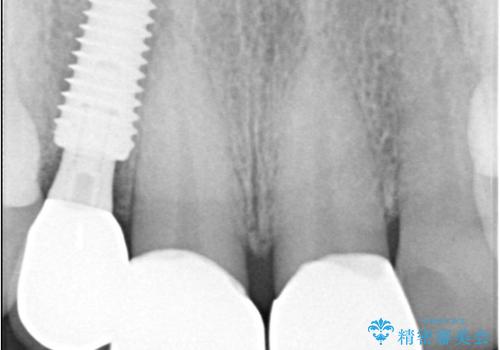

インプラント治療は、低侵襲で短期間に行える「抜歯即時インプラント治療」を選択しました。

この方法は、抜歯したその日にインプラントを埋入し、手術が1回で済むのが大きな特徴です。

治療期間も短く、抜歯からわずか3か月でオールセラミッククラウンを装着することができます。

- 税込110万円(インプラントの手術代+オールセラミッククラウン5年保証×3本+静脈内鎮静代全て込み)費用は治療当時の料金となります